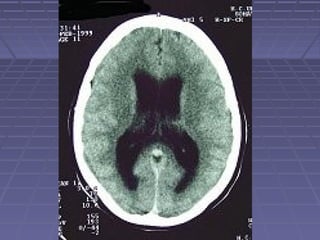

 TAC de cráneoTAC de cráneo si: persisten o aumentan lassi: persisten o aumentan las

manifestaciones clínicas, se sospechamanifestaciones clínicas, se sospecha

herniación, persiste la fiebre.herniación, persiste la fiebre.

 TC: hidrocefalia, lesiones vasculares,TC: hidrocefalia, lesiones vasculares,

tuberculomastuberculomas